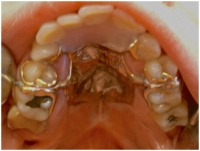

På klinikken fremstiller vi ganespalteprotester, også kaldet obturatorproteser.

De består af en ganeplade der dækker ganespalten mellem mundhulen og næsehulen. Ved at lukke ganespalten forhindres passage fra mundhulen til næsehulen, og det skaber en bedre lydresonans i udtalen.